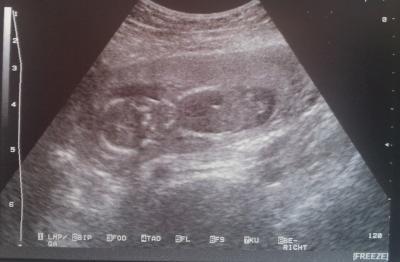

Hallo zusammen, erst einmal SORRY, dass ich mich hier so selten melde. Lese immer fleißig mit, aber bin irgendwie immer noch so ängstlich, dass ich selten schreibe. Will hier auch niemanden verunsichern. Ich hoffe ja, dass das auch noch irgendwann nachlässt. Ich war am Montag nach laaaaangen vier Wochen auch endlich wieder beim Arzt. Es war alles soweit in Ordnung. Der Arzt war zufrieden und das Kleine hat sich auch ordentlich bewegt und Purzelbäume geschlagen. Das Geschlecht konnte man noch nicht erkennen. Ich hoffe, dass wir es dann nach Weihnachten, den 27. beim 3D-Ultraschall erfahren. Vorher haben wir noch einen normalen Termin am 16.12. Irgendwie konnte er auch die Größe gar nicht mehr so genau bestimmen. War das bei euch auch so? Er hatte jetzt erst so 9,1 geschätzt, was ja ein paar mm zu wenig wären und hat dann aber 9,5 auf das US-Bild geschrieben. Irgendwie denke ich zwar, dass ich mir keine Sorgen machen sollte, aber irgendwie hören die einfach nicht auf. Mein Bauch fängt auch so langsam an zu wachsen und ich glaube es erscheint langsam auch diese Linea Negra. Hat das noch jemand von euch? Ganz liebe Grüße an euch alle!! Ella

Bild zu Montag FA-Termin - Forum für Mai - Mamis